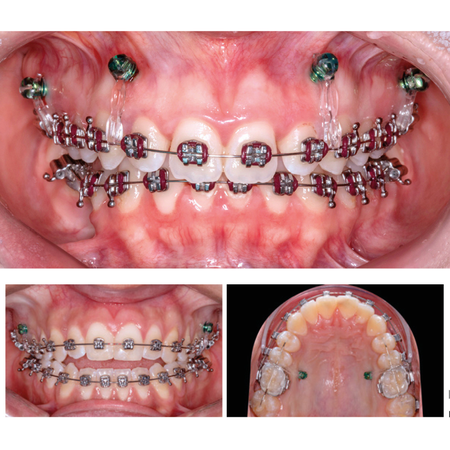

Challenges of treating patients with vertical discrepancies: clinical approaches using mini-implants

INTRODUCTION: Adult patients are increasingly seeking orthodontic treatment without resorting to orthognathic surgery. In some cases, whether anterior open bite or deep bite, mini-implants can be used to provide the patient with a more stable occlusion and a significant improvement in their clinical condition. OBJECTIVE: Two clinical cases with vertical problems will be presented, which benefited from the use of mini-implants, avoiding orthognathic surgery approaches. METHODS: Different...